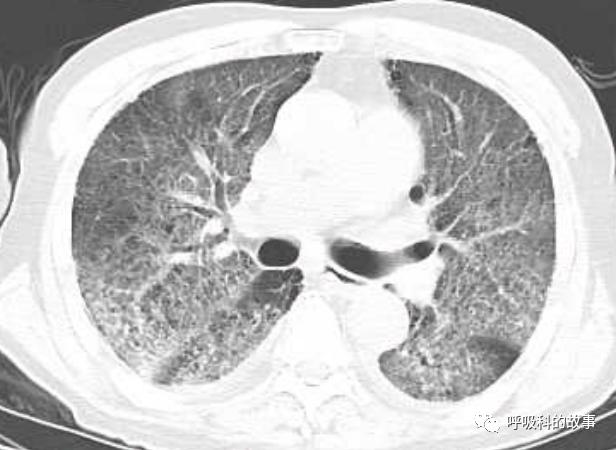

上周,我去会诊一个病人又出现了类似的情况,一个72岁的男性病人因为发生十二指肠球部溃疡穿孔入住我院胃肠外科,给予腹腔镜下十二指肠球部溃疡穿孔修补术。术后由于患者禁食就给予了大量的补液,大约有3000多毫升,其中0.9%氯化钠盐水(也就是我们通常所说的生理盐水)一共是补了接近2000ml,同时还补了1500ml的营养液呢。患者术后第二天晚上开始出现呼吸困难,程度进行性加重,到了术后的第五天,呼吸困难非常明显了,病人也出现端坐位呼吸,两肺出现严重的肺水肿转入ICU治疗。